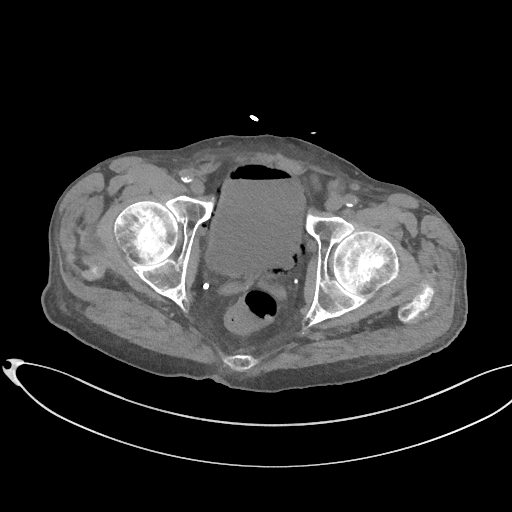

Figurile 1 şi 2: axial examinare CT abdomen şi pelvis fără substanță de contrast

Video 1: axial examinare CT abdomen şi pelvis fără substanță de contrast

Discuţie caz nr 131: pacient de 85 de ani cunoscut diabetic este adus la camera de gardă pentru dureri abdominale difuze, efectueaza CT fără substanță de contrast deoarece eGFR este 21 mL/min/1.73 m². Se evidențiază pericardita în cantitate medie, mai multe chiste renale – unul spontan hiperdens, multiple plăci aterotrombotice calcificate la nivelul aortei și ramurilor precum și multiple bule aerice în peretele vezicii urinare și conținut hidro-aeric al vezicii urinare. Ultimele două elemente sugerează diagnosticul de cistita emfizematoasă.